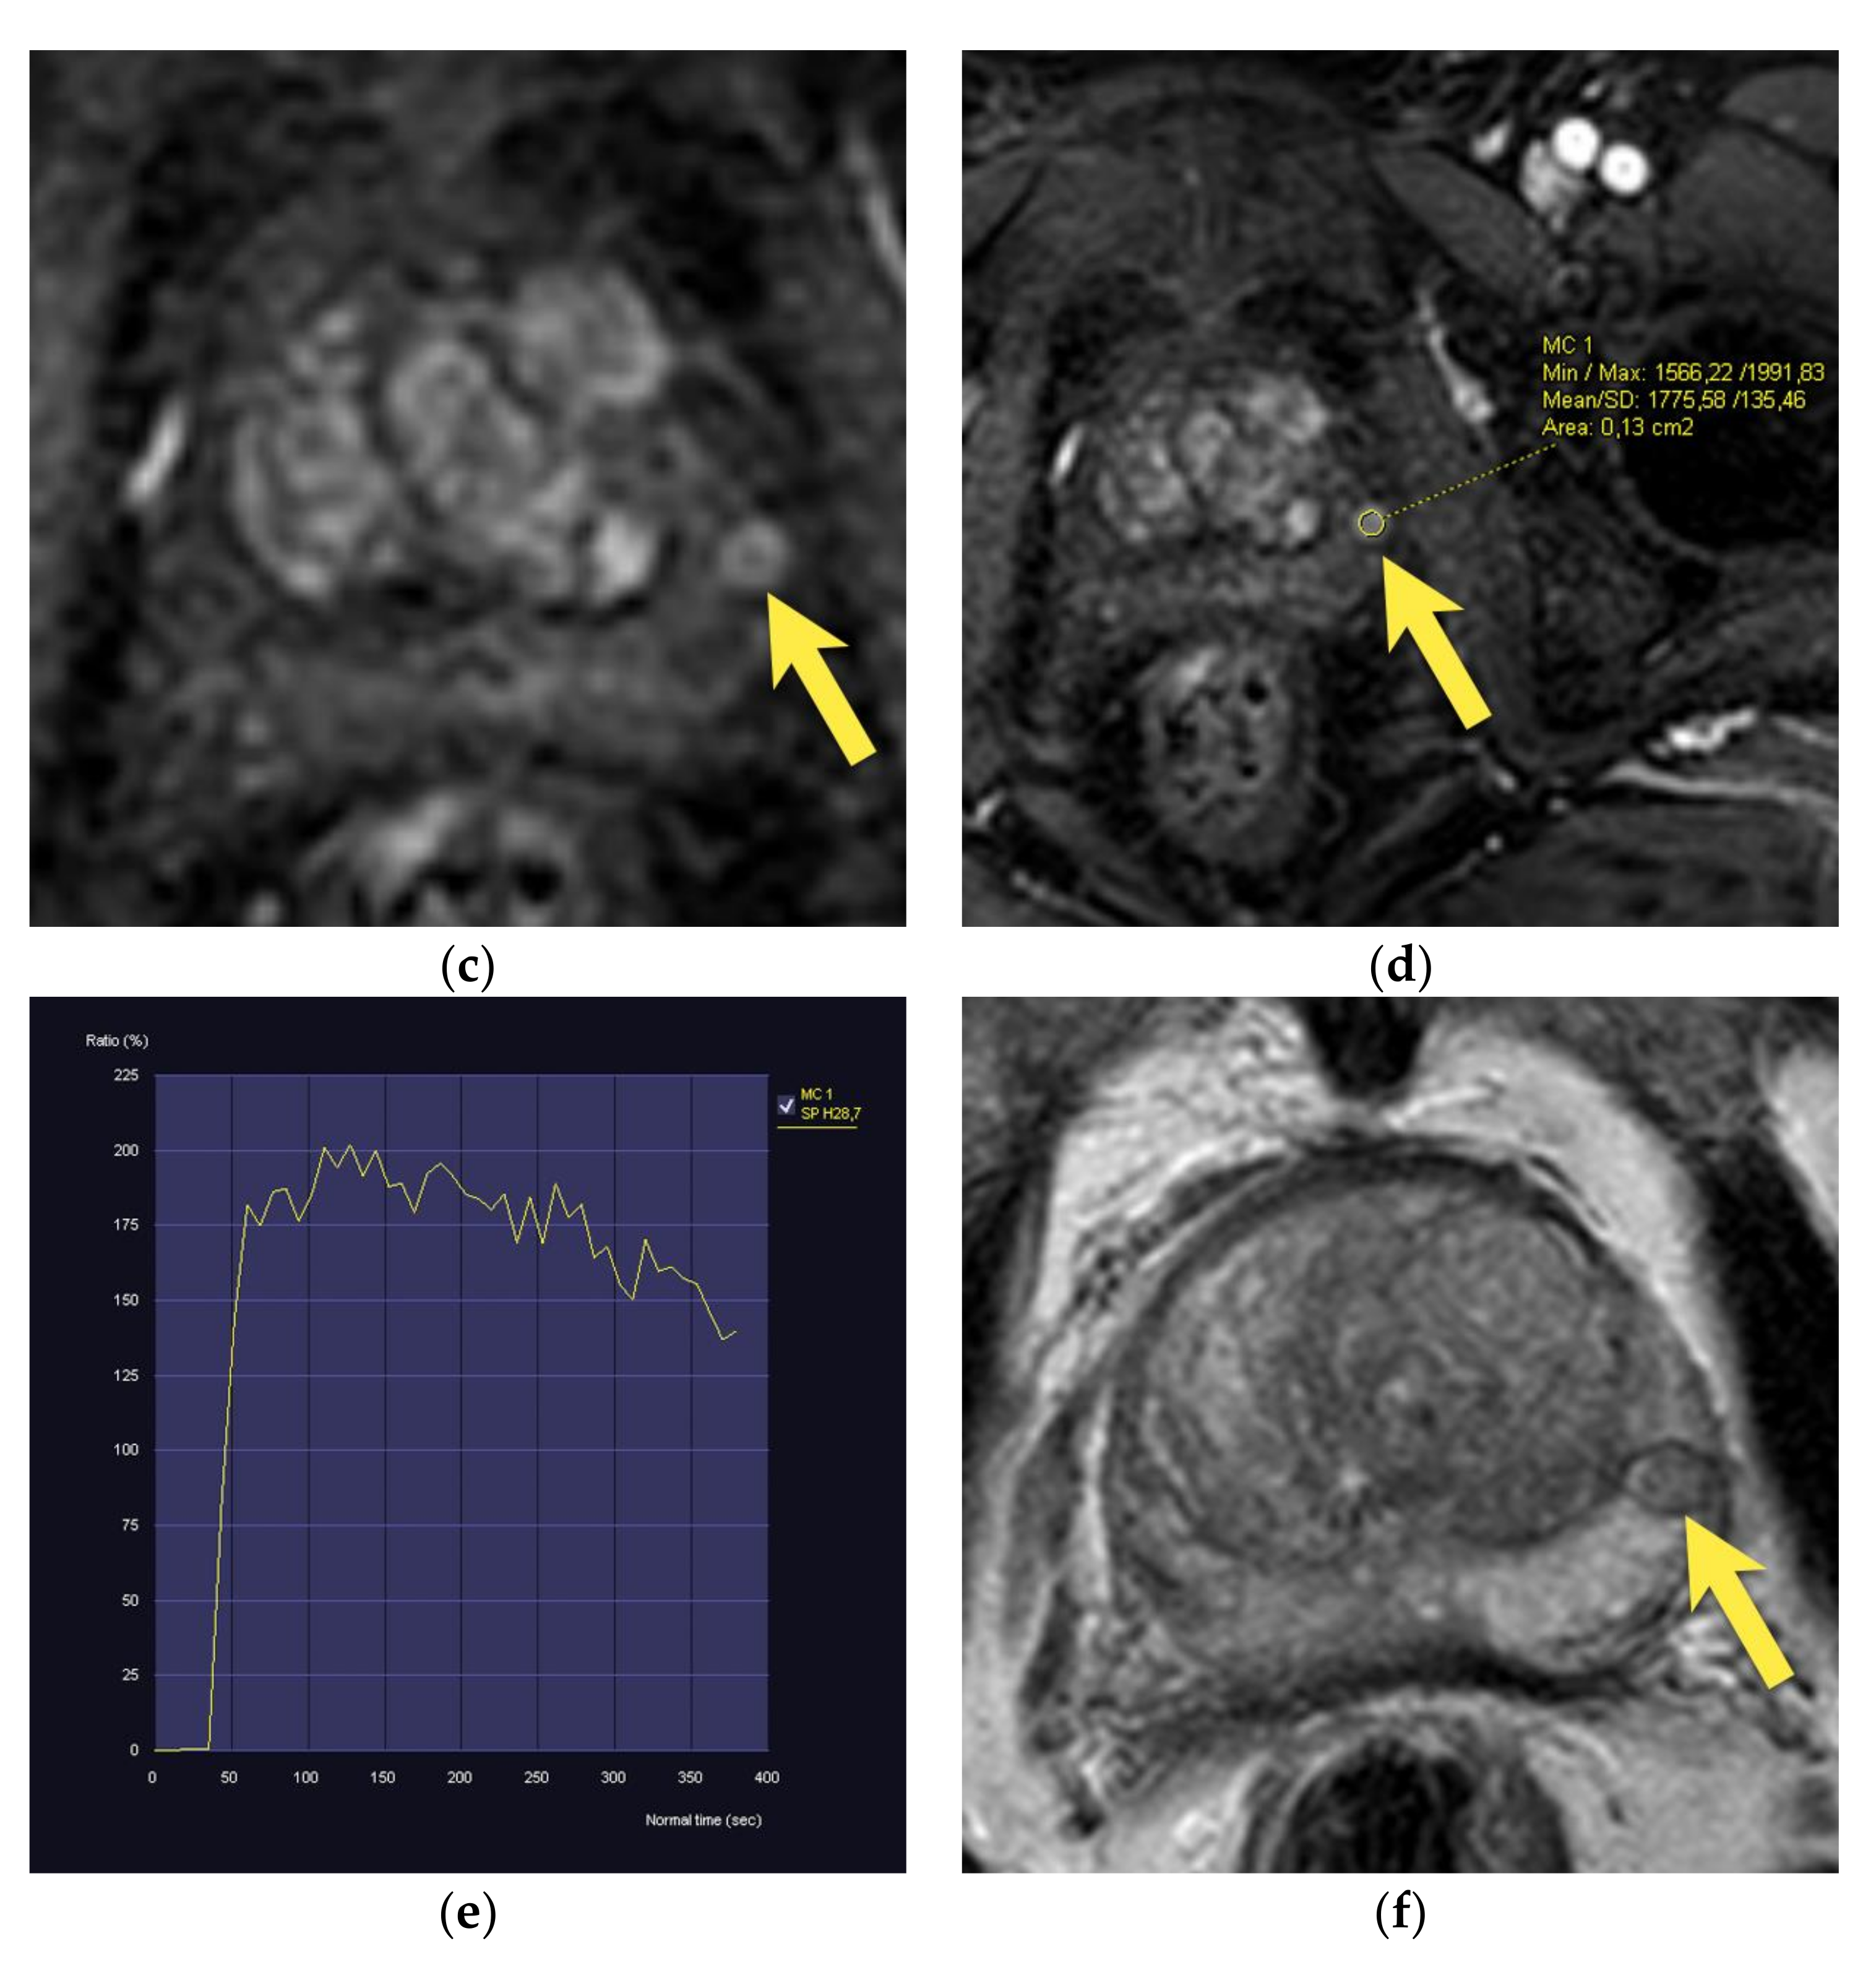

10. Prostatic Abscess

11. Quality of Images